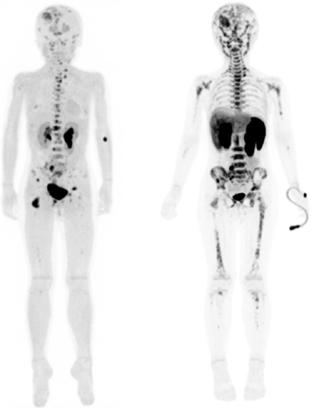

El neuroblastoma es la neoplasia sólida extracraneal más frecuente en niños. Al momento del diagnóstico, el 50% de los pacientes presentan enfermedad metastásica. Estos pacientes tienen un alto riesgo de enfermedad refractaria o recurrente y un pronóstico adverso. Durante las últimas décadas, la medicina nuclear ha sido fundamental para la estadificación y la evaluación de la respuesta al tratamiento del neuroblastoma. Actualmente, la técnica de imagen nuclear estándar es la gammagrafía corporal total con meta-[ 131I ]yodobencilguanidina ([ 131I ]mIBG) en México, generalmente combinada con tomografía computarizada por emisión monofotónica con tomografía computarizada (SPECT-CT). Sin embargo, el 10% de los neuroblastomas no son ávidos por este radiofármaco y las imágenes con [131I]mIBG tienen una resolución espacial relativamente baja, lo que resulta en una sensibilidad limitada para lesiones más pequeñas, además de conferir mayor dosis de radiación al paciente. Se necesitan métodos más precisos para evaluar la extensión total del neuroblastoma debido a su comportamiento y variabilidad tumoral heterogénea con el fin de optimizar las estrategias de tratamiento. La imagen híbrida ha llevado a la introducción de radiotrazadores compatibles con la tomografía por emisión de positrones (PET) en neuroblastomas, como [ 124 I]mIBG, [18F]mFBG, [18 F]FDG, [ 18F]Octreotide, 6[18F]F-DOPA y [11 C]mHED. La metodología PET ofrece mayores y múltiples ventajas sobre la SPECT, incluida una resolución superior y un rango tomográfico de cuerpo entero, además del beneficio de la información en las diversas secuencias al combinarlo con la resonancia magnética.

Figura 1A) Estudio PET con 6-[18F]FDOPA positivo para actividad tumoral del primario conocido en abdomen y retroperitoneo, con metástasis difusas en la médula ósea del esqueleto axial y apendicular.

Figura 1B) Estudio PET con [18F]OCTREOTIDE con sobreexpresión anormal de los receptores de somatostatina en retroperitoneo y esqueleto axial y apendicular.

Al correlacionar con 6-[18F]DOPA (Figura 1A) se observa que las lesiones tienen mayor sobreexpresión de los receptores de somatostatina.

El objetivo de este caso es mostrar la precisión diagnóstica que ofrecen los diversos radiofármacos, al realizar una correcta elección de acuerdo a la naturaleza biológica del neuroblastoma y a su expresión molecular.

CASO CLÍNICO

Femenino de 7 años con diagnóstico de Neuroblastoma, se realiza PET/RM con [18F]F-DOPA para estadiaje, con evidencia de lesión primaria a nivel de retroperitoneo y conglomerados locoregionales así como infiltración a médula ósea del esqueleto axial y apendicular (Figura 1A), posteriormente la paciente fue tratada quirúrgicamente con resección de la lesión primaria así como tratamiento con inmunoterapia y transplante autólogo de médula ósea además de radioterapia. Al presentar refractariedad al tratamiento comentado, se plantea la posibilidad de administrar Lutecio (177Lu) oxodotreotide, por lo que se sugiere realizar PET/RM con [18F]Octreotide para valorar expresión de receptores de somatostatina y considerar la terapia con radionúclidos para receptores de péptidos (PRRT), el estudio muestra evidencia de sobreexpresión anormal de dichos receptores en retroperitoneo, espacio subpleural izquierdo además de esqueleto axial y apendicular (Figura 1B).

Los tejidos malignos mayormente desdiferenciados son ávidos por 2-[ 18 F]FDG debido a una mayor tasa de metabolismo de la glucosa (Figura 2). El PET con 2-[ 18 F]FDG se utiliza cada vez más en neoplasias malignas pediátricas, incluido el neuroblastoma. Varios estudios han confirmado que la mayoría de las lesiones de neuroblastoma concentran 2-[18F]FDG, el cual se acumula en el neuroblastoma no ávido de mIBG. El 2- [18F]FDG se recomienda como reempla-

zo de [131I]mIBG en la evaluación del neuroblastoma mIBG-negativo o débilmente mIBG-positivo, y como modalidad complementaria cuando las imágenes radiológicas o los hallazgos clínicos sugieren una enfermedad más extensa que la revelada por las imágenes [131 I]mIBG. Con el desarrollo de otros blancos moleculares específicos para la detección de lesiones en neuroblastoma, entre ellos; [18F] Octreotide y 6[18F]F-DOPA (Figura 3) se puede obtener mayor especificidad y sensibilidad que la gammagrafía convencional con [ 131 I] mIBG, además de menor exposición a la radiación principalmente en glándula tiroides.

Figura 2A) Estudio PET con 2[18F]-FDG, positivo para captación del radiofármaco en esqueleto axial y apendicular en un paciente con diagnóstico de Neuroblastoma de 9 años.

Figura 2B) Estudio PET/RM con 2[18F]-FDG donde se identifican las lesiones funcionales con corregistro anatómico en esqueleto axial y apendicular. Estas imágenes denotan un neuroblastoma de estirpe probablemente desdiferenciada y de pobre pronóstico.

Estudio PET con 6-[18F]DOPA 3A) y [18F]OCTREOTIDE 3B) en cortes coronales de secuencias T2 de miembros pélvicos y con imágenes fusionadas, donde se identifica mayor sobreexpresión anormal de los receptores de somatostatina al compararlos con 6-[18F]DOPA, y que hace candidata a la paciente para PRRT.